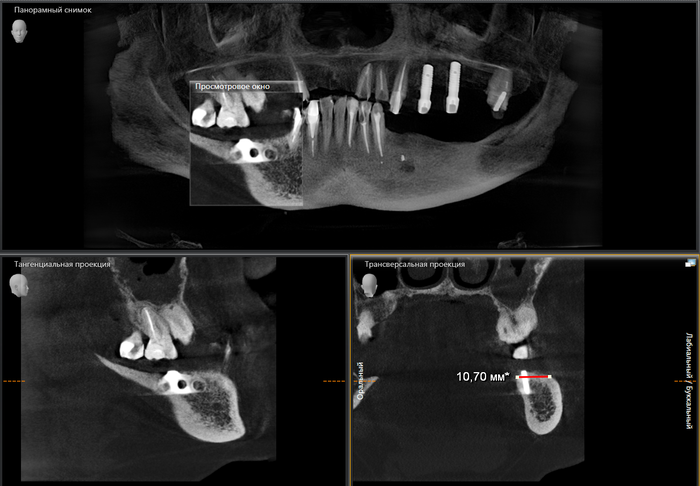

Для того, чтобы оценить на сколько правильно был установлен имплантат, потребуется компьютерная томография - 3дЭ объемный снимок.

А для того, что ортопантомография (ОПТГ, обзорный или панорамный снимок зубов), является плоскостным, а значит происходит наложение каждой детали снимка послойно друг на друга. Следовательно, рассмотреть область проведенной или планируемой операции, объем костной ткани по ширине и высоте, расположение нижнечелюстного нерва или верхнечелюстной пазухи, во всех плоскостях, под иным углом или другой проекции невозможно . КЛКТ (Конусно-лучевая компьютерная томография), напротив, дает нам такую возможность.

Выглядит этот снимок примерно так:

Кстати, это компьютерная томография до операции той самой пациентки, чей случай я рассматривал в самом начале. Согласитесь, почему бы не удалить зуб и сразу не установить имплантат, к чему все эти "выжидания" после удаления? "Профессора" скажут - риски! А вдруг то, а вдруг это. А вдруг челюсть отвалится или стоять не будет. Скажу так, риски есть всегда и везде, но поверьте, при правильном планировании и наличии навыков их не больше, чем при классической имплантации.